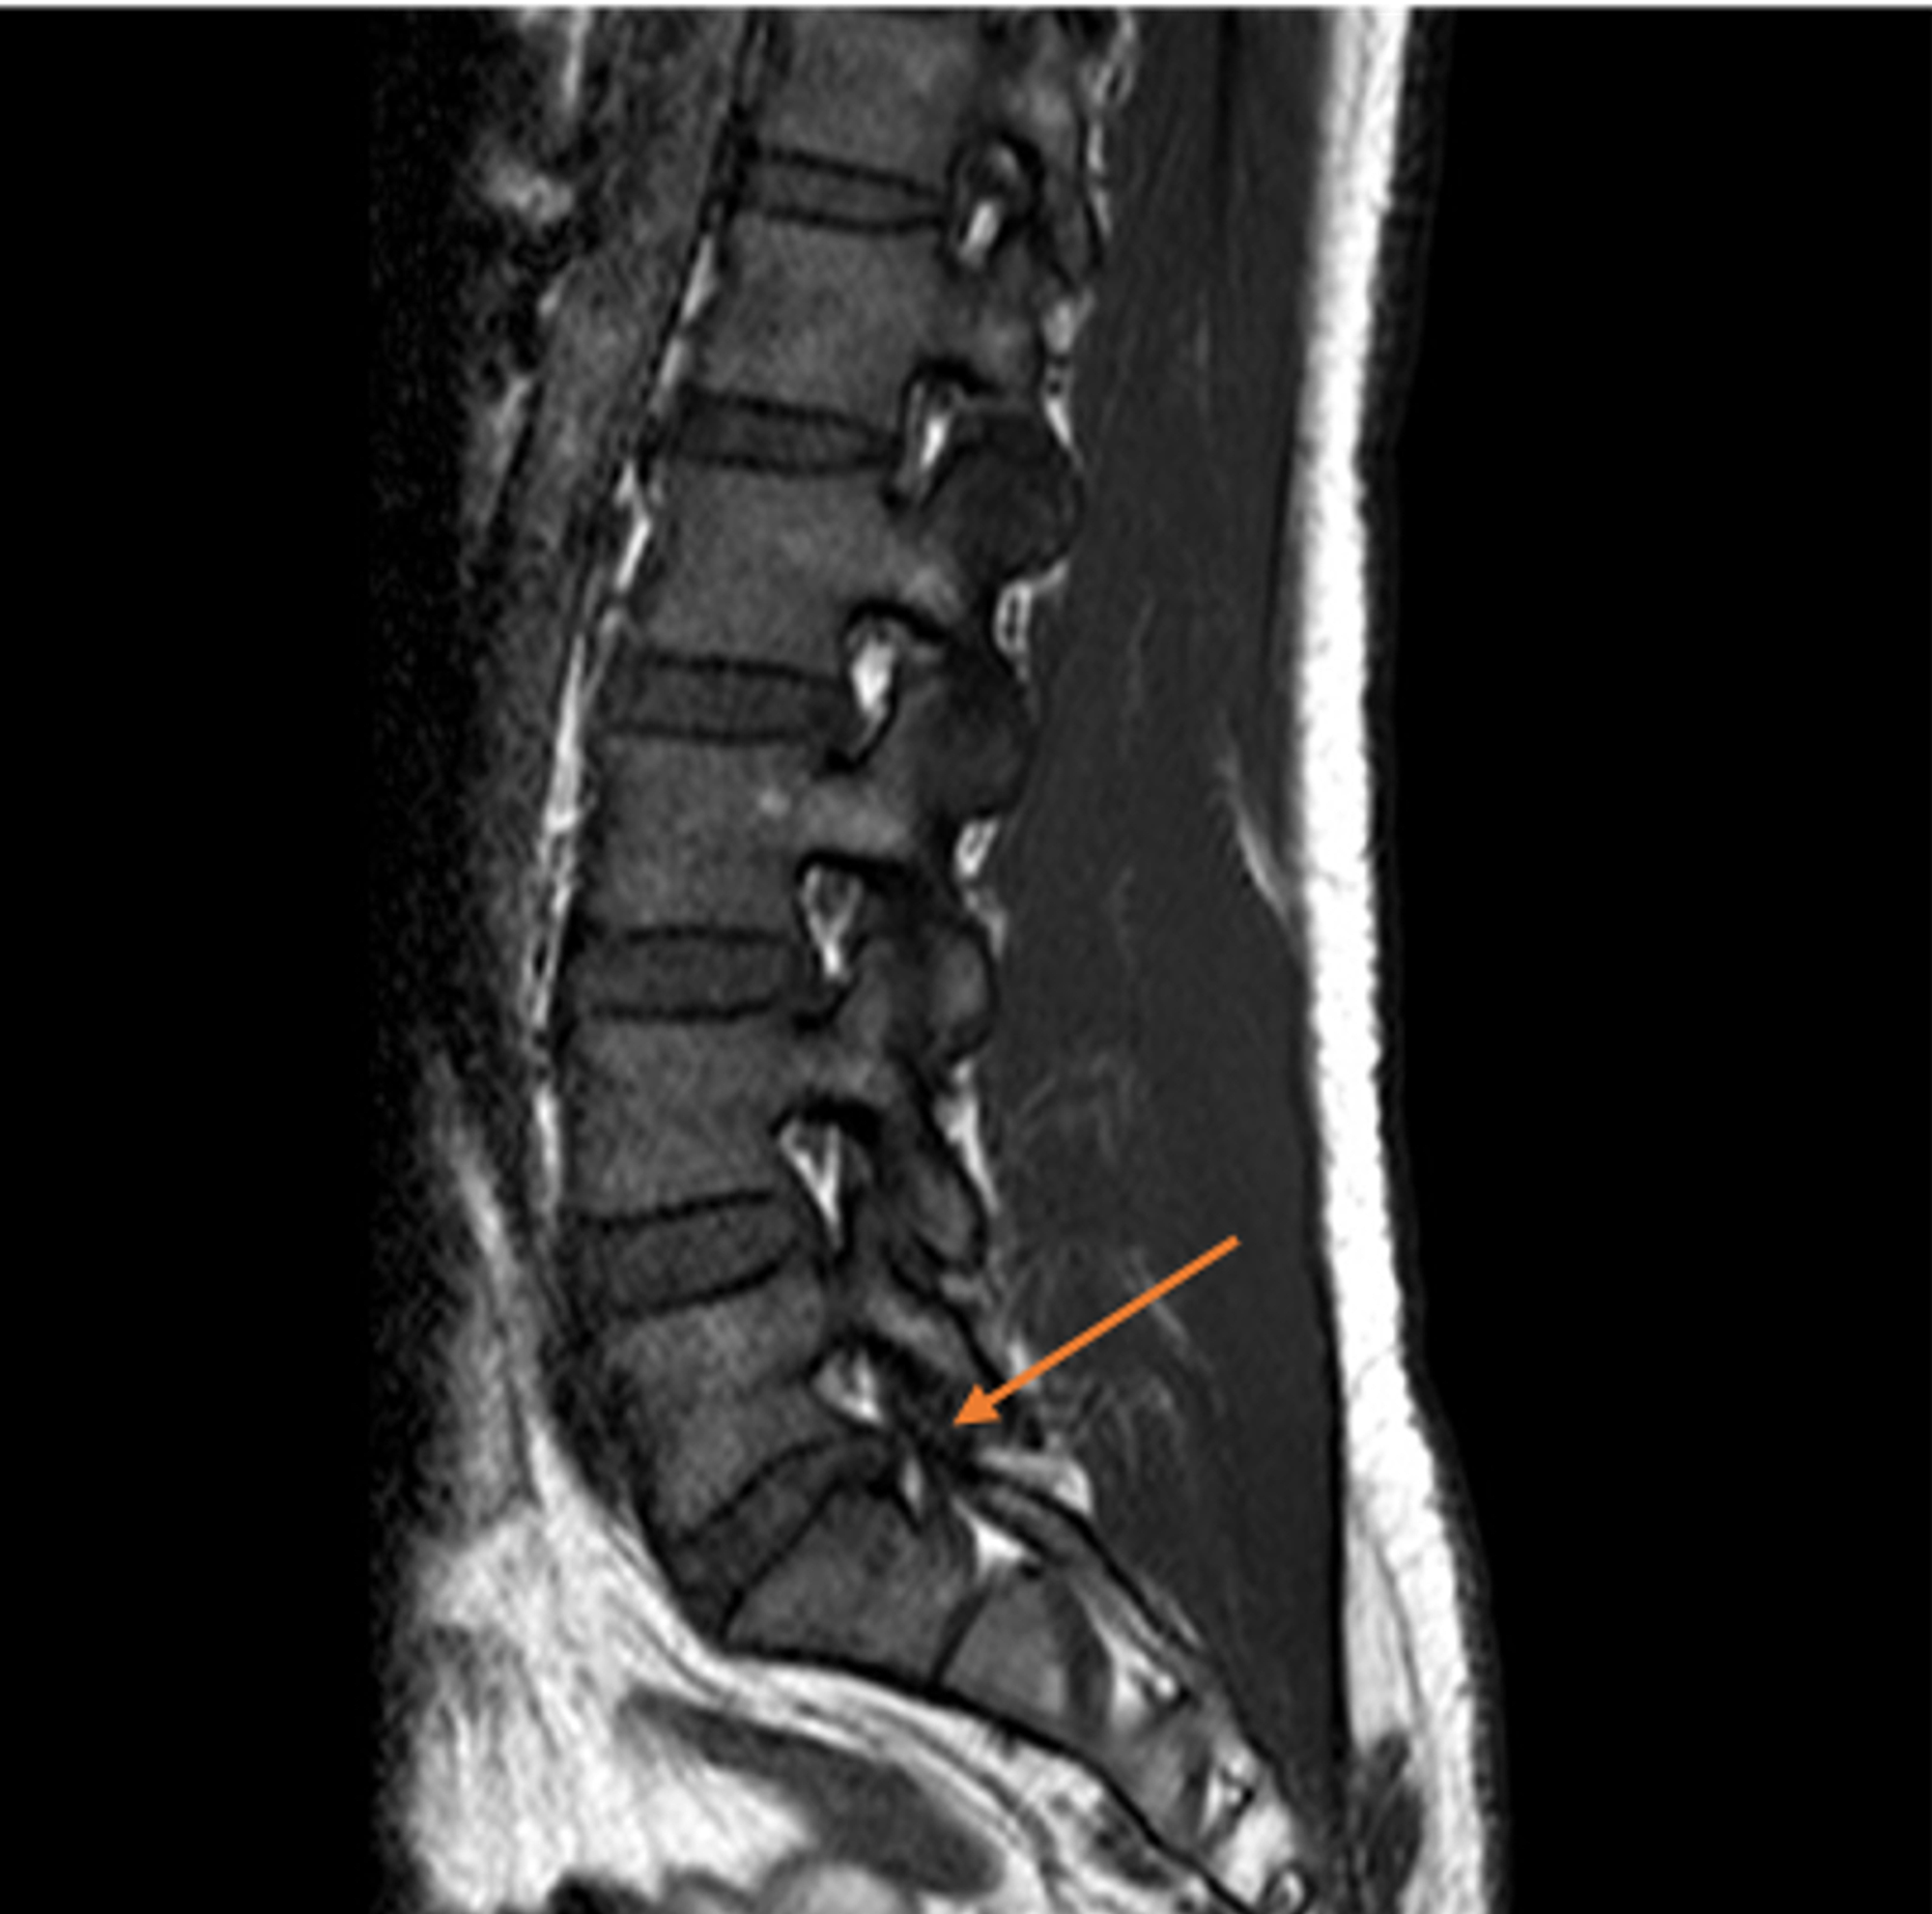

Progression of lumbar disc degeneration over a decade a heritability What Is Degenerative Disc Disease Lumbar degenerative disc disease is a condition where one or more discs in your back lose their strength. what is degenerative disc disease? degenerative disc disease is a condition characterized by the gradual deterioration of the discs that act as cushions between the vertebrae in. One of the more unfortunate aspects of getting older is that your joints. What Is Degenerative Disc Disease Lumbar.